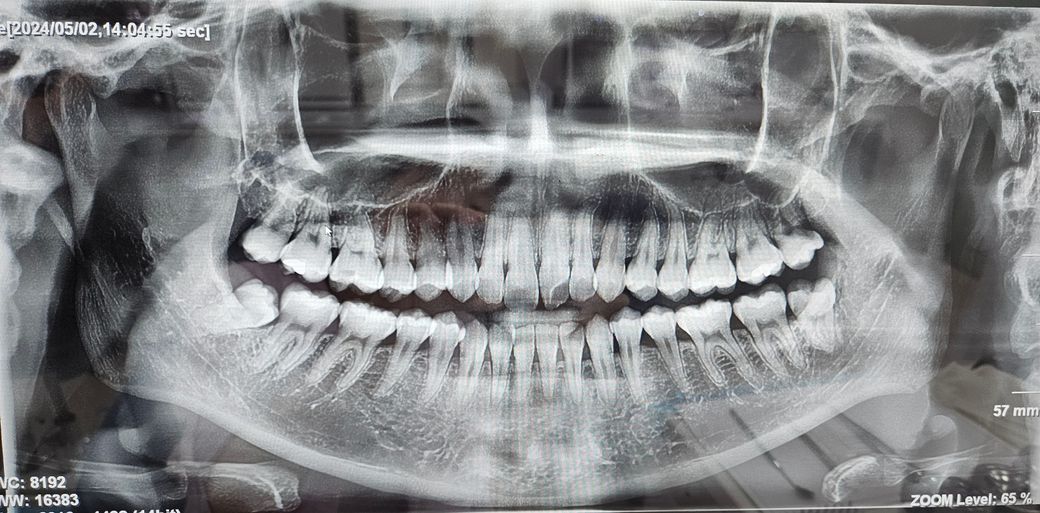

현재 사랑니 4개가 난 상황입니다.각 사랑니별 발치 난이도가 어떻게 될까요?

며칠전 치과에서 CT를 찍었는데 사랑니가 윗니, 아랫니 각각 2개씩 4개가 나있었습니다.

1. 각 사랑니별 발치 난이도와 통증 강도가 어떻게 될까요? (형태가 심각한 상태인지 궁금합니다ㅠㅠ)

1. 오른쪽 아래 사랑니 발치가 조금 어려울 것으로 보이며 나머지는 크게 어렵지 않아 보입니다.

맹출 양상을 보면 사진기준 왼쪽 아래 사랑니 제외하고는 예방적으로 빼줘야 하는건 없습니다 관리잘해서 충치가 안생기게 해주면 안빼도됩니다

-사랑니 4개다 크게 어려운 사랑니 발치는 아닌거 같습니다.

-오른쪽 아래 사랑니는 비스듬이 맹출되어 있어서 앞치아까지 충치가 진행될수 잇으니 이 치아는 빼시는게 좋을것같습니다.

오른쪽 아래 있는 사랑의 경우에는 기울어져 나 있기 때문에 발치 난이도가 다른 것보다 높을 것으로 생각됩니다 다른 차들은 똑바로 나와 있기 때문에 발치를 하는데 크게 문제가 되지는 않습니다